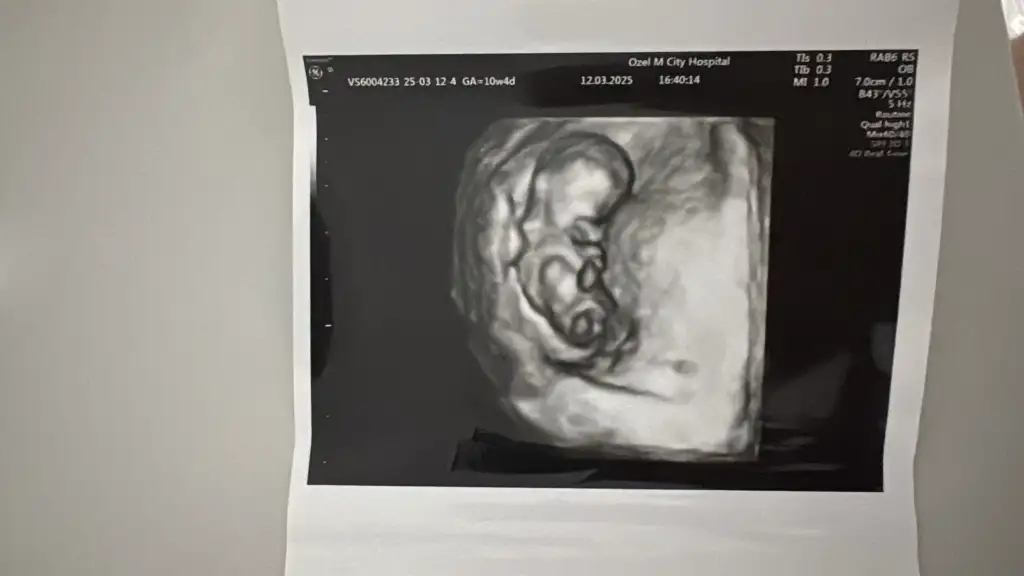

Merhaba kizlar.12 hafta 2 günlük hamileyim.bugun doktor kontrolümüz vardı.doktor baya uğraştı cinsiyeti görebilmek tahminde bulunmak için.net birşey söyleyemem dedi.yanilma payı bu haftalarda çok yüksek dedi.cikinti gibi birşey var ama net birşey söyleyemem dedi.nub teorisini bilen arkadaşlar yorum yapabilir misiniz ? Kız da olsa erkek de olsa çok heyecanlıyımrabbim hepimizin bebeklerini sağlıkla kucağımiza almayı nasip etsin inşallah

Bir sonrakk konttolde belli olur bana da oyle dedi benim de 12 hafta 5 gunlukMerhaba kizlar.12 hafta 2 günlük hamileyim.bugun doktor kontrolümüz vardı.doktor baya uğraştı cinsiyeti görebilmek tahminde bulunmak için.net birşey söyleyemem dedi.yanilma payı bu haftalarda çok yüksek dedi.cikinti gibi birşey var ama net birşey söyleyemem dedi.nub teorisini bilen arkadaşlar yorum yapabilir misiniz ? Kız da olsa erkek de olsa çok heyecanlıyımrabbim hepimizin bebeklerini sağlıkla kucağımiza almayı nasip etsin inşallah